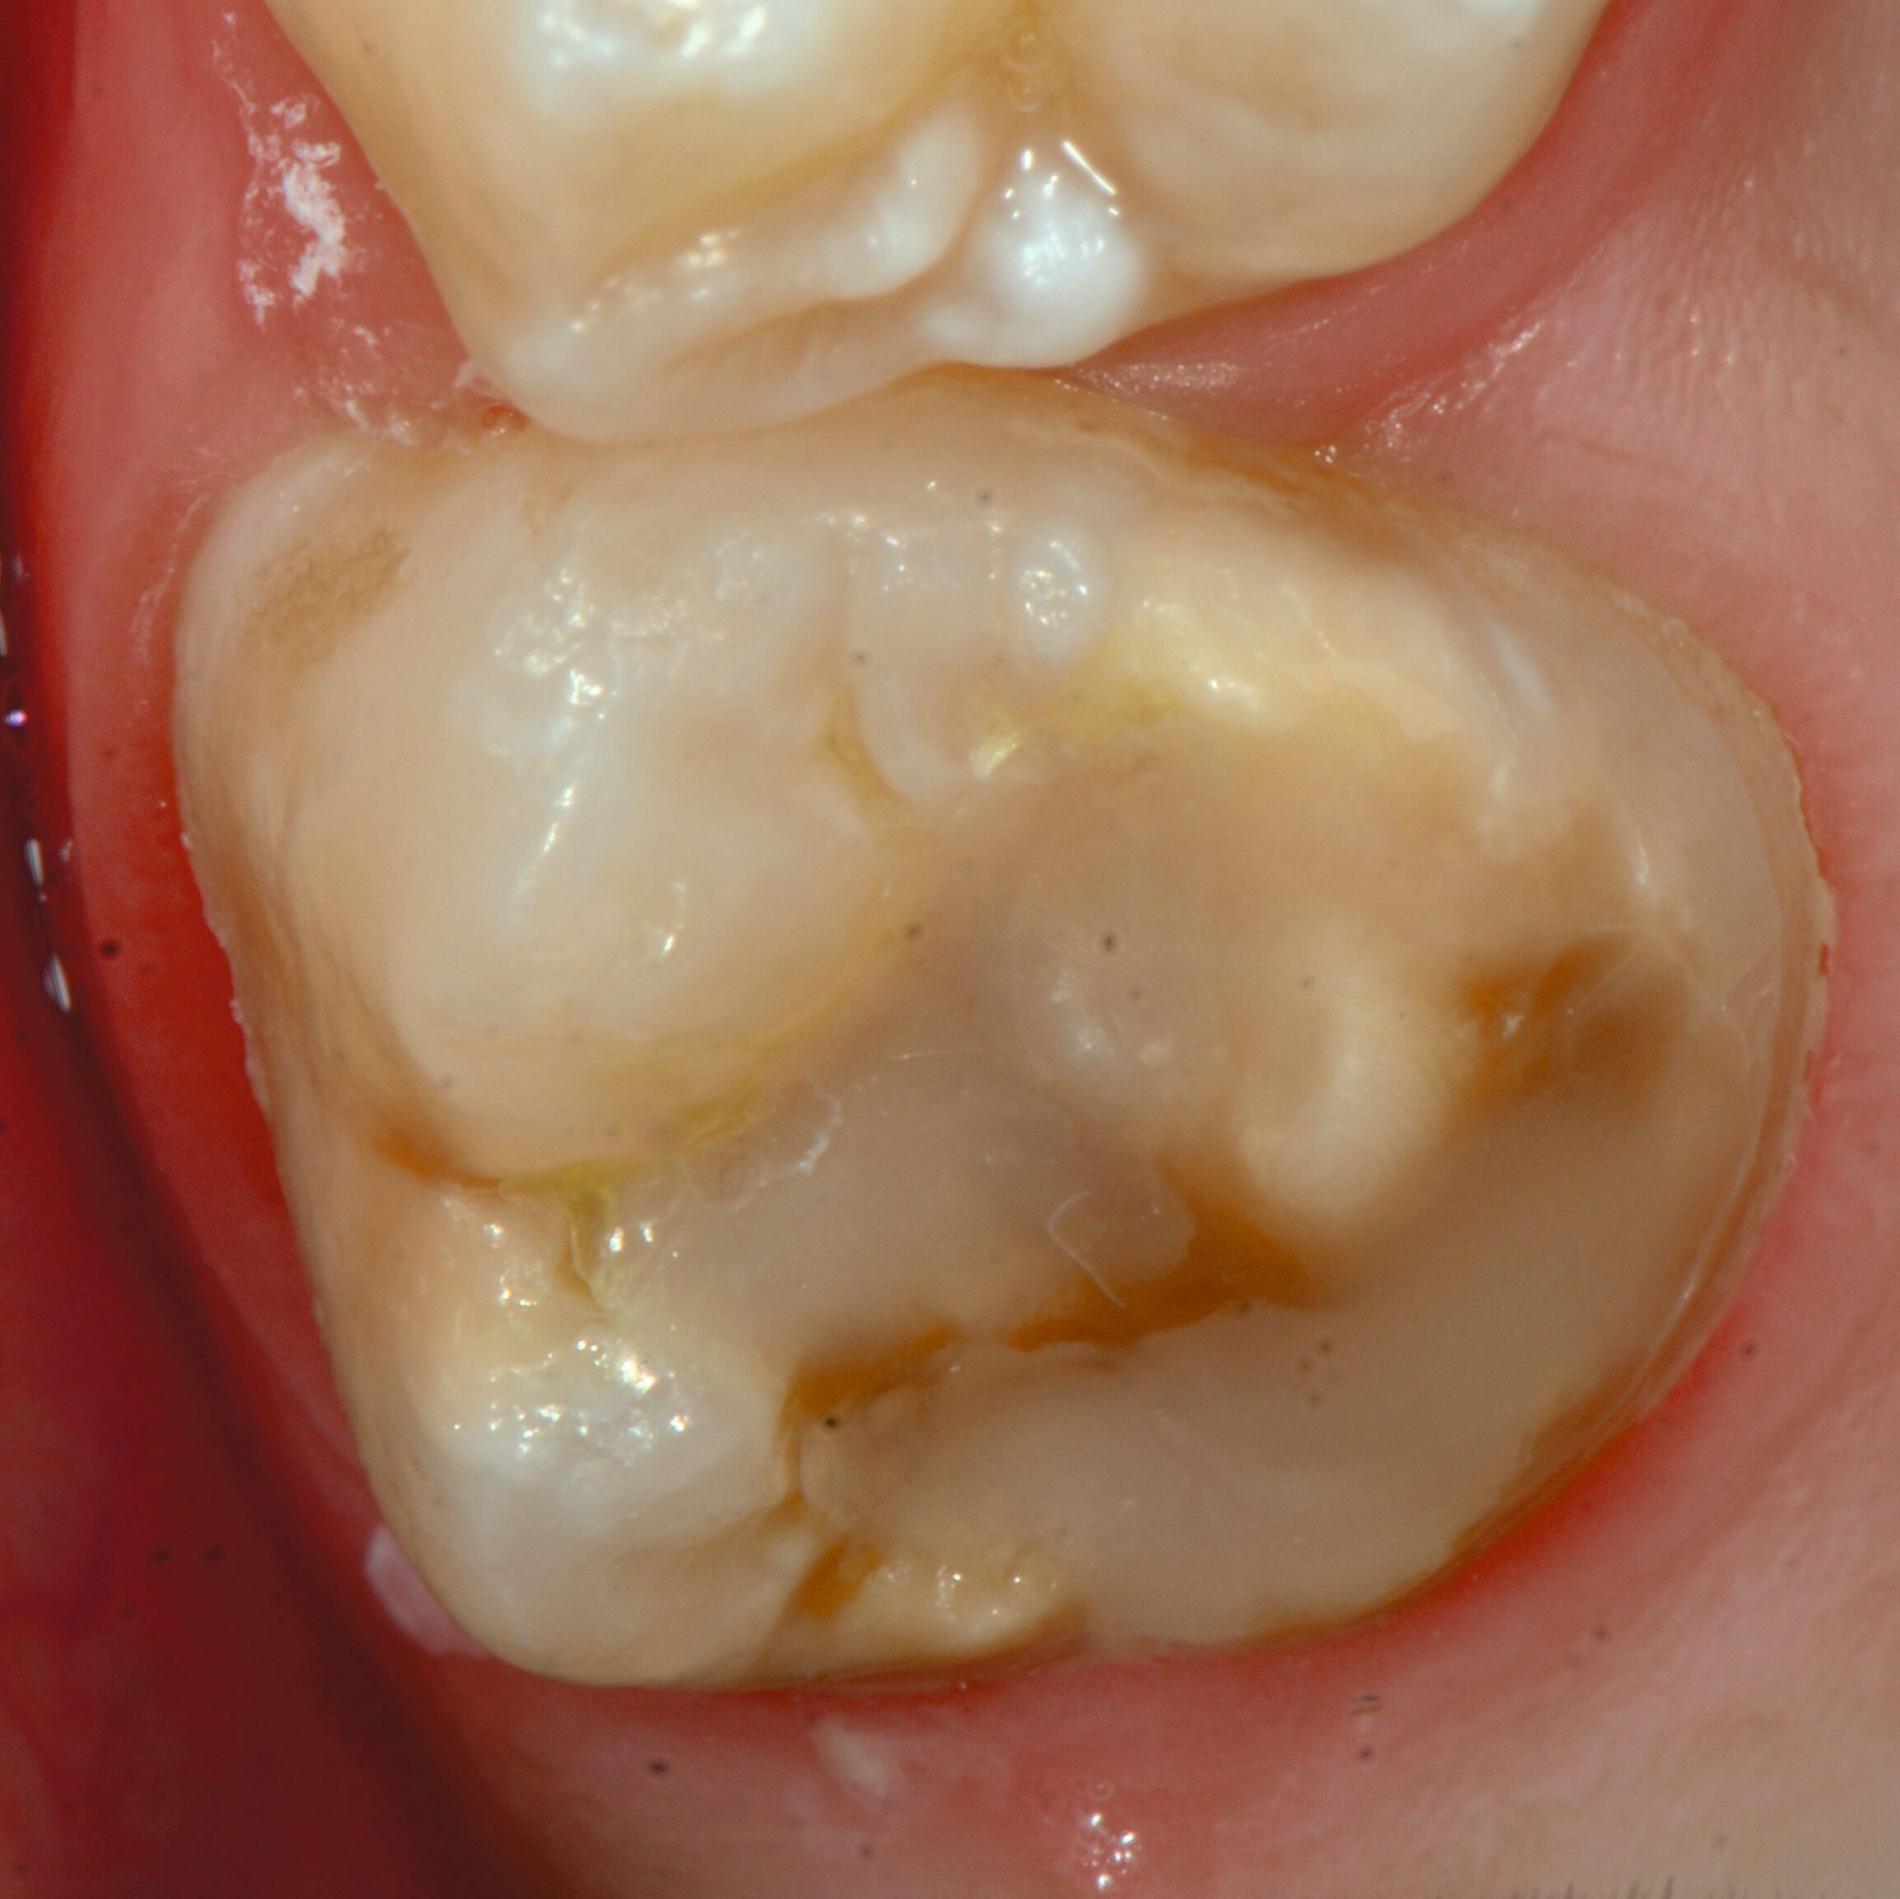

Das klinische Erscheinungsbild an bleibenden Zähnen zeigt typischerweise weißlich-gelbe bis gelblich-braune Opazitäten, die zumindest in einigen Bereichen durch eine scharfe Abgrenzung (engl.:„demarcated opacities“) zum gesunden Zahnschmelz charakterisiert sind (Abbildungen 3 und 4). Die abgegrenzten Hypomineralisationen befinden sich mehrheitlich im Bereich der inzisalen Kronenhälfte unabhängig von dem Auftreten an Front- oder Seitenzähnen. Die Ausprägung am Zahn kann dabei auf einzelne Areale oder Höcker begrenzt sein.

An umfangreich hypomineralisierten Zähnen können Schmelzeinbrüche (engl.: „enamel breakdown“ oder „enamel desintegration“, Abbildung 5) auftreten [Lygidakis et al., 2010; 2022]. Da diese oftmals die Folge einer fehlenden Belastungsfähigkeit des Zahnschmelzes sind und erst nach der Einstellung der Zähne in die Okklusion auftreten, werden sie auch als posteruptive Schmelzeinbrüche bezeichnet. Sie sind häufig im Bereich der Kauflächen beziehungsweise Höcker der Molaren zu finden, führen zur Dentinexposition und damit einhergehend zu ausgeprägten Hypersensitiven insbesondere bei Kindern, deren Zähne gerade erst durchgebrochen sind [Linner et al., 2021].

Für die Dokumentation und Klassifikation der MIH wurden verschiedene Systeme vorgeschlagen. Als historisch und veraltet gilt der (modifizierte) DDE-Index. Demgegenüber haben die Kriterien der EAPD – abgegrenzte Opazitäten (Abbildung 3 und 4), Schmelzeinbrüche (Abbildung 5), atypische Restaurationen (Abbildung 6) – mittlerweile die weiteste Verbreitung gefunden. Diese wurden 2003 erstmals zur Beschreibung der MIH auf empirischer Basis publiziert [Weerheijm et al., 2003] und den Jahren 2010 und 2022 im Rahmen der damaligen MIH-Workshops bestätigt [Lygidakis et al., 2010; 2022].